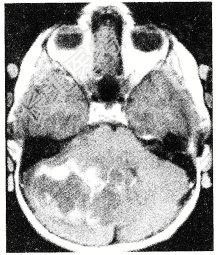

- 单项选择题颅后窝肿瘤(如图所示)临床症状应不包括

A、交叉性麻痹

B、同侧后组脑神经损伤症状

C、Romberg征多为阴性

D、轮替试验幅度增大

E、Romberg下肢远端的共济失调